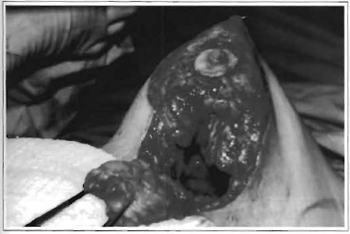

Fig. 5a -Preoperative assessment: 43 year-old, with invasive ductal carcinoma on L breast.

Fig.5b - 6-month postoperative period. Sectorectomy with skin resection on upper quadrant and use of lower pedicle flap as an island on the upper quadrant of left side breast. Note mimitization with adjacent skin. Reduction of about 280 g of L breast combined with sectorectomy of R breast to attain symmetry, providing similar volume for both breasts (Group IV -special cases).